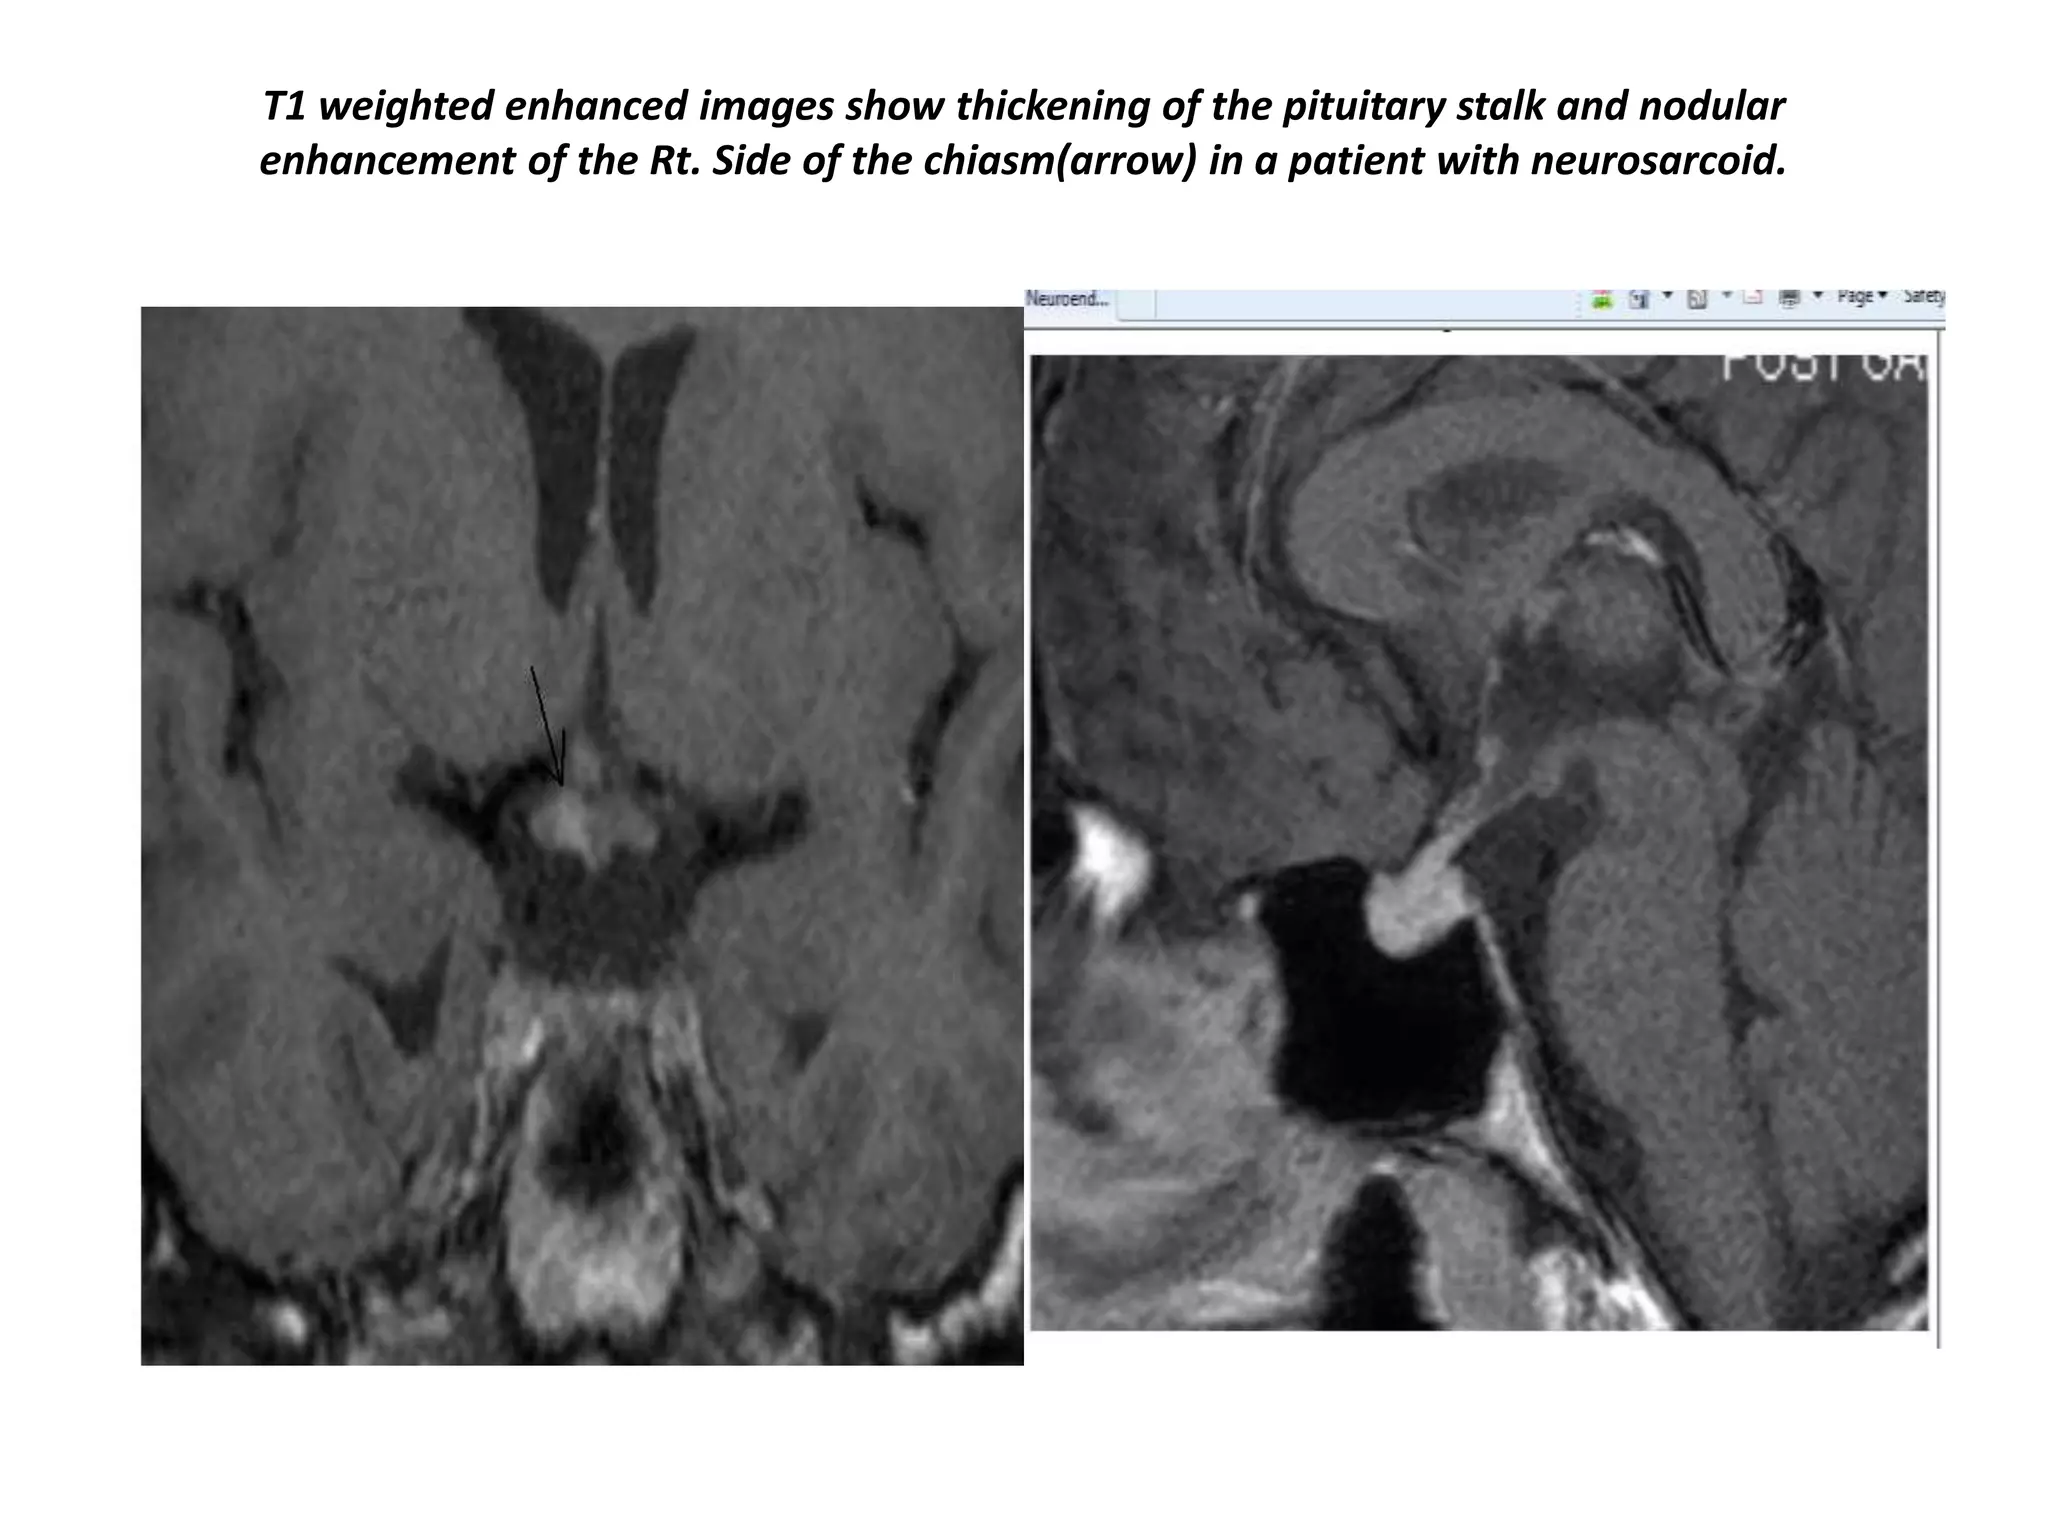

T1 weighted enhanced images show thickening of the pituitary stalk and nodular

enhancement of the Rt. Side of the chiasm(arrow) in a patient with neurosarcoid.